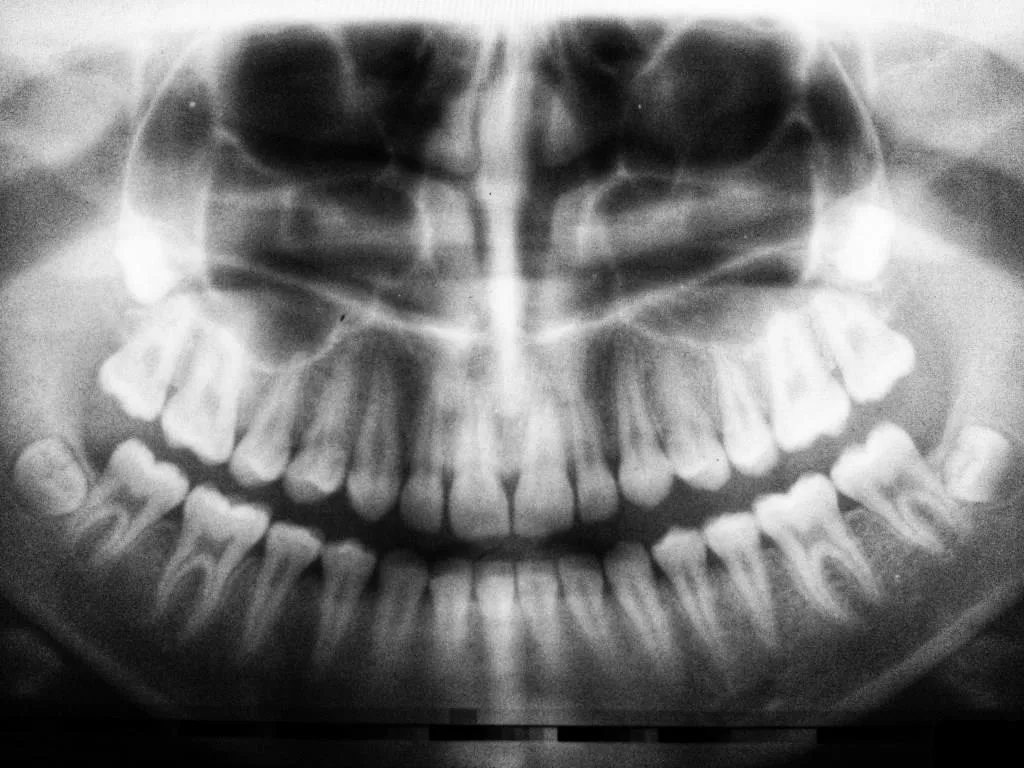

El bruxismo es un trastorno que afecta a una gran parte de la población, y sus consecuencias pueden ser severas. Este hábito involuntario de apretar o rechinar los dientes puede llevar a un desgaste dental significativo, así como a problemas en la articulación temporomandibular (ATM).

- Desgaste visible en los dientes, como superficies planas o bordes desgastados.

El diseño de la férula de descarga es fundamental para su eficacia. Este dispositivo se adapta a la forma de los dientes del paciente, lo que permite una correcta alineación y evita el contacto directo entre las superficies dentales. Esto ayuda a prevenir el desgaste y el dolor asociado al bruxismo.